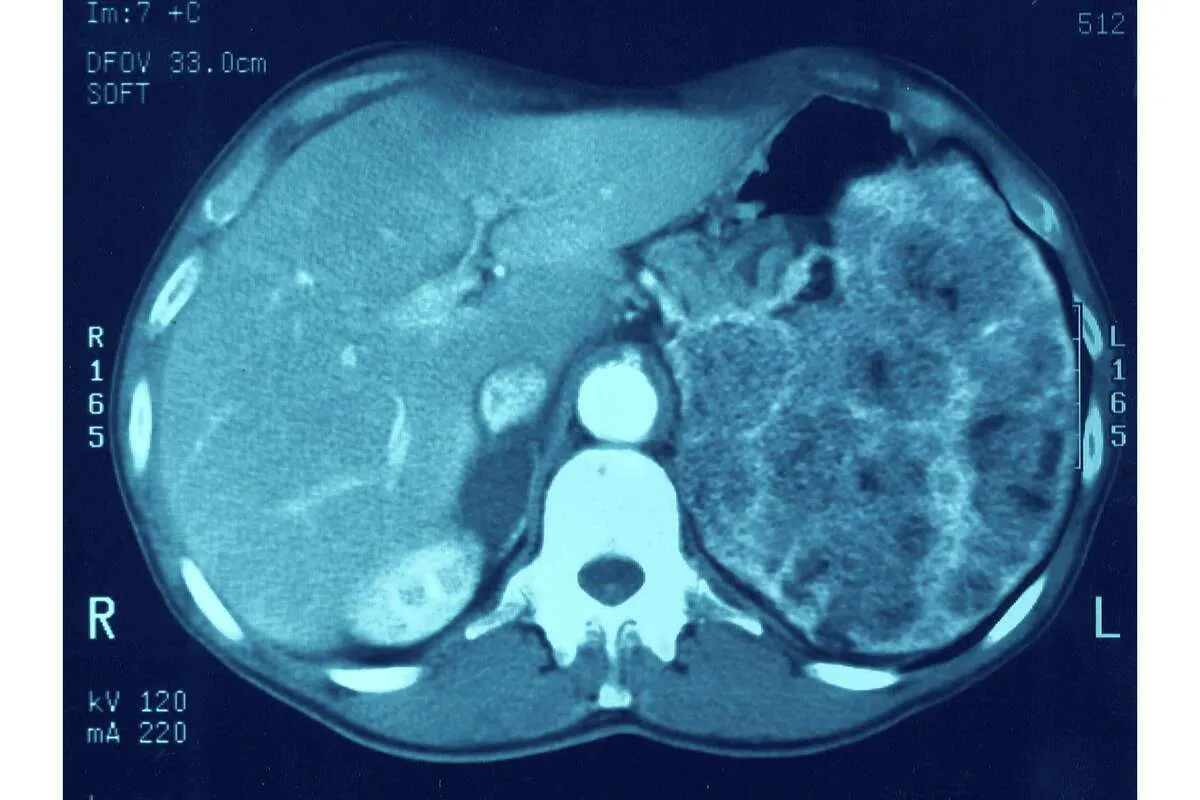

Изображения КТ-сканирования (Images of a Cat Scan)

Изображения, полученные при КТ-сканировании, играют ключевую роль. Они помогают врачам обнаруживать и лечить болезни.

Интерпретация КТ-изображений

Интерпретация КТ-изображений требует знания анатомии и патологии. Врачи-рентгенологи анализируют изображения, чтобы выявить аномалии, такие как опухоли, травмы или инфекции.

На изображении ниже показано, как КТ-сканер производит изображения внутренних структур:

В заключении, изображения КТ-сканирования являются мощным инструментом в медицинской диагностике. Они позволяют врачам получать детальную информацию о внутренних органах и тканях.